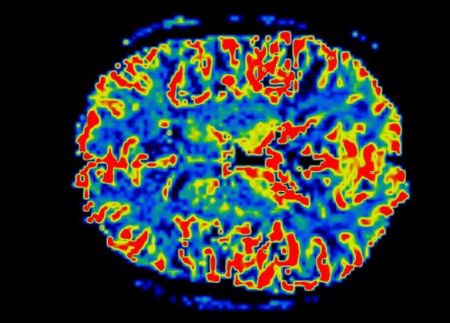

Ενα πρωτοποριακό μοντέλο Τεχνητής Νοημοσύνης που αναπτύχθηκε από ερευνητές του ΕΚΠΑ «λύνει» τα χέρια των γιατρών – Σε τρία χρόνια εκτιμάται ότι θα ξεκινήσει η πιλοτική εφαρμογή του διαγνωστικού «έξυπνου» εργαλείου